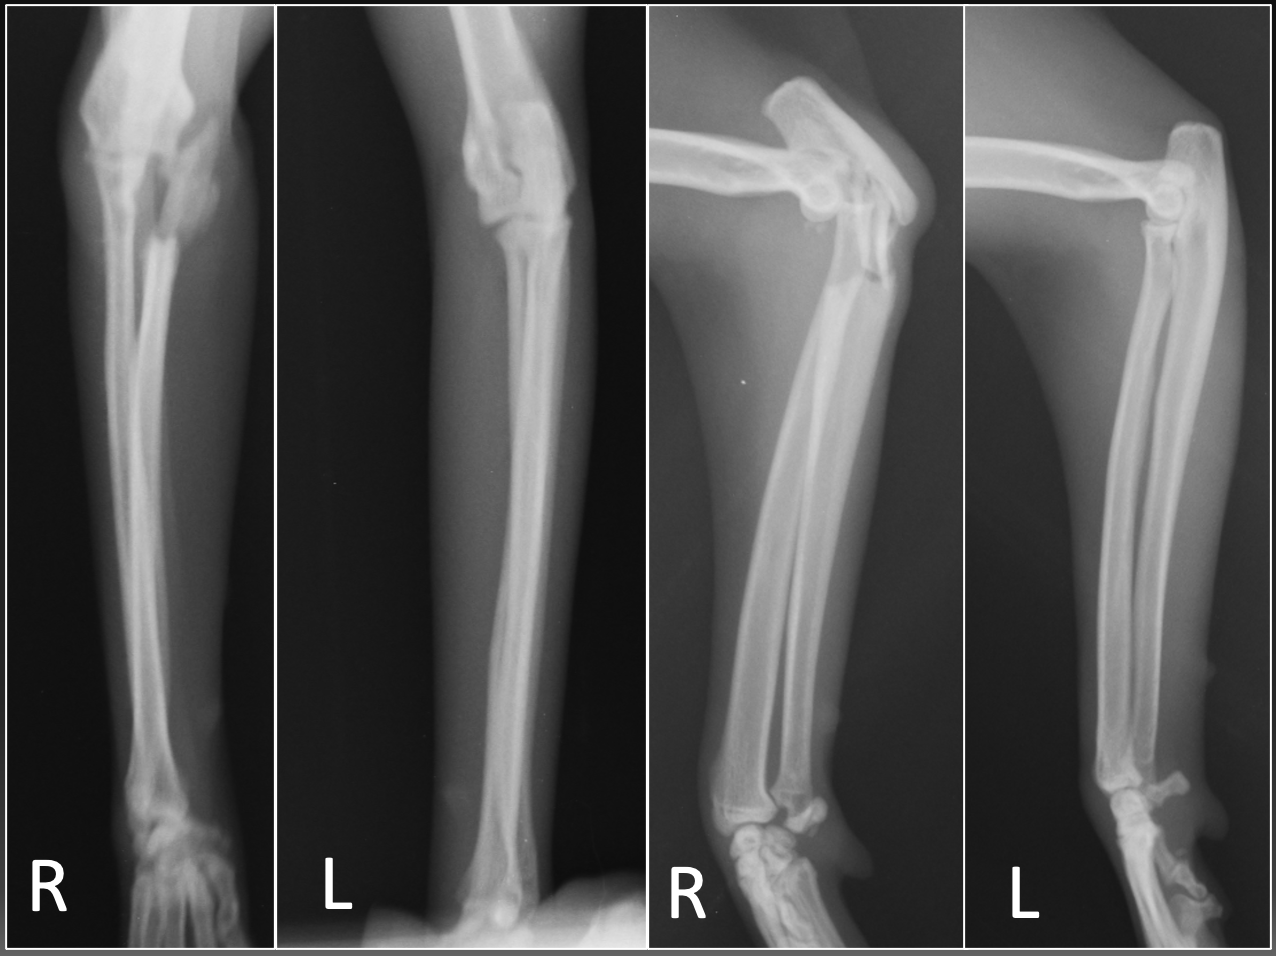

症例は雑種の避妊雌、推定3歳、体重4.3kgの猫です。保護猫のため詳細は不明ですが、1ヶ月以上前から右前肢を挙上しているとのことで来院されました。 来院時のX線画像検査所見です。右側の尺骨の関節内粉砕骨折および、橈骨頭の尾側変位が確認されました。尺骨鈎状突起から遠位にかけて多数の骨片を伴う骨折が認められました。このように関節内が粉砕している場合には、元通りにきっちりと全てを戻すことは困難です。

来院時のX線画像です。肘の部分の骨が折れてしまっているのがわかると思います。骨折の仕方からタイプ2モンテジア粉砕骨折と診断しました。